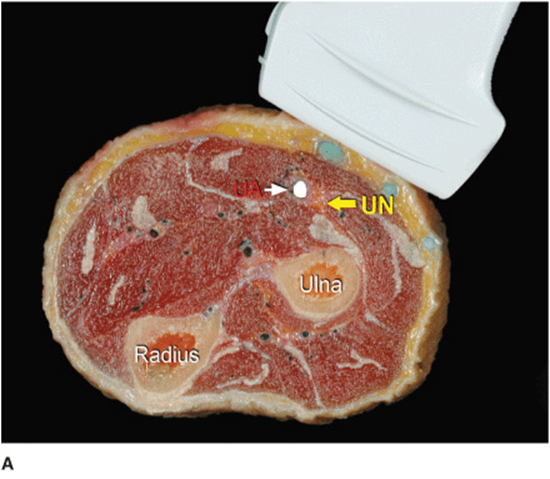

The ulnar nerve can be easily imaged in the midforearm, immediately medial to the ulnar artery, which acts as a useful landmark. Similar to the radial and median nerves, the ulnar nerve appears as a hyperechoic stippled structure, with a triangular to oval shape (Figure 33-5A and B). The ulnar artery and nerve separate, when the transducer is slid more proximally on the forearm, with the artery taking a more lateral and deeper course. The ulnar nerve can be traced easily proximally toward the ulnar notch, when desired, and the level of the blockade can be decided based on the desired distribution of the anesthesia as well as the ease of imaging and accessing the nerve. Sliding the transducer distally shows the nerve and artery becoming progressively shallower together as they approach the wrist where the ulnar nerve lies medial to the artery.

FIGURE 33-5. (A) Anatomy of the ulnar nerve at the midforearm. The ulnar nerve (UN) is closely related to the ulnar artery (UA). (B) Sonoanatomy of the ulnar nerve at the midforearm. UN is shown closely related to the UA, sandwiched between the flexor carpi ulnaris (FCUM) and flexor digitorum profundus muscles (FDPM). FDSM = Flexor Digitorum Superficialis Muscle.